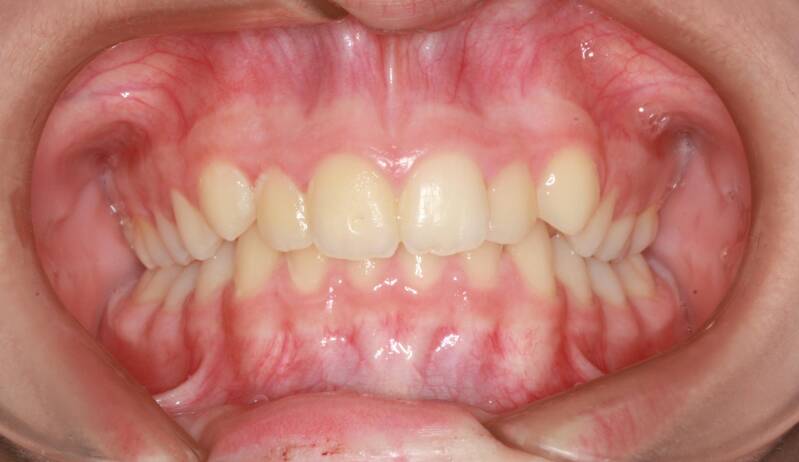

Questo mese vi presentiamo G.G. f. di15aa. Ha una seconda classe suddivisione destra molare e canina. richiesta Allineamento.

FOTO INIZIALI PRE TRATTAMENTO ORTODONTICO